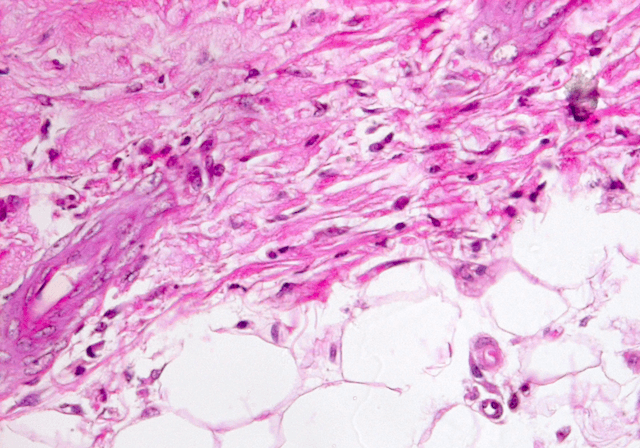

Histopathological Image Analysis of White Blood Cells

Sample Images

The project is to identify and count the White Blood Cells in a Skin Tissue. Firstly, we have to differentiate between RBCs, WBCs and Platelets. Not only that, we have to take into account, the presence of hair follicle in the skin sample. Then, WBCs have been identified, we have to further classify WBCs into their aforementioned types. The classification will be done on the basis of the number of nucleus in the types of WBCs. Lastly, the count can be categorized as to be within, above or below the normal count of 4,500 to 11,000 microliter. Thus, identifying whether or not the sample is infected or not.

Our new approach will be to dive into Fully Convolutional Neural Networks for the task of “Semantic Image Segmentation”. Semantic Image Segmentation is the task of segmenting an image and coloring the segmented parts with the color of the classification class. We will adopt the technique on biological data and first make a CNN to segment our image and then move forward with the semantic analysis task. Making it a 2 way process will help us deal with the difficulties step by step. This novel approach of segmenting on cell level with CNN is an experiment that may give unlikely result. We are exploring various other techniques side by side since the task is tedious and accuracy is highly important.